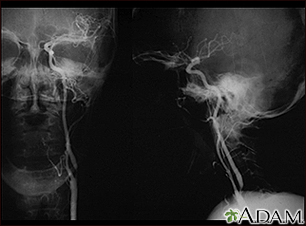

Carotid stenosis - X-ray of the left artery - illustration

A carotid arteriogram is an X-ray study designed to determine if there is narrowing or other abnormality in the carotid artery, a main artery to the brain. This is an angiogram of the left common carotid artery (both front-to-back and side views) showing a severe narrowing (stenosis) of the internal carotid artery just beyond the division of the common carotid artery into the internal and external branches.

Carotid stenosis - X-ray of the left artery

illustration

Carotid stenosis - X-ray of the right artery - illustration

This is an angiogram of the right carotid artery showing a severe narrowing (stenosis) of the internal carotid artery just past the carotid fork. There is enlargement of the artery or ulceration in the area after the stenosis in this close-up film. Note the narrowed segment toward the bottom of the picture.

Carotid stenosis - X-ray of the right artery